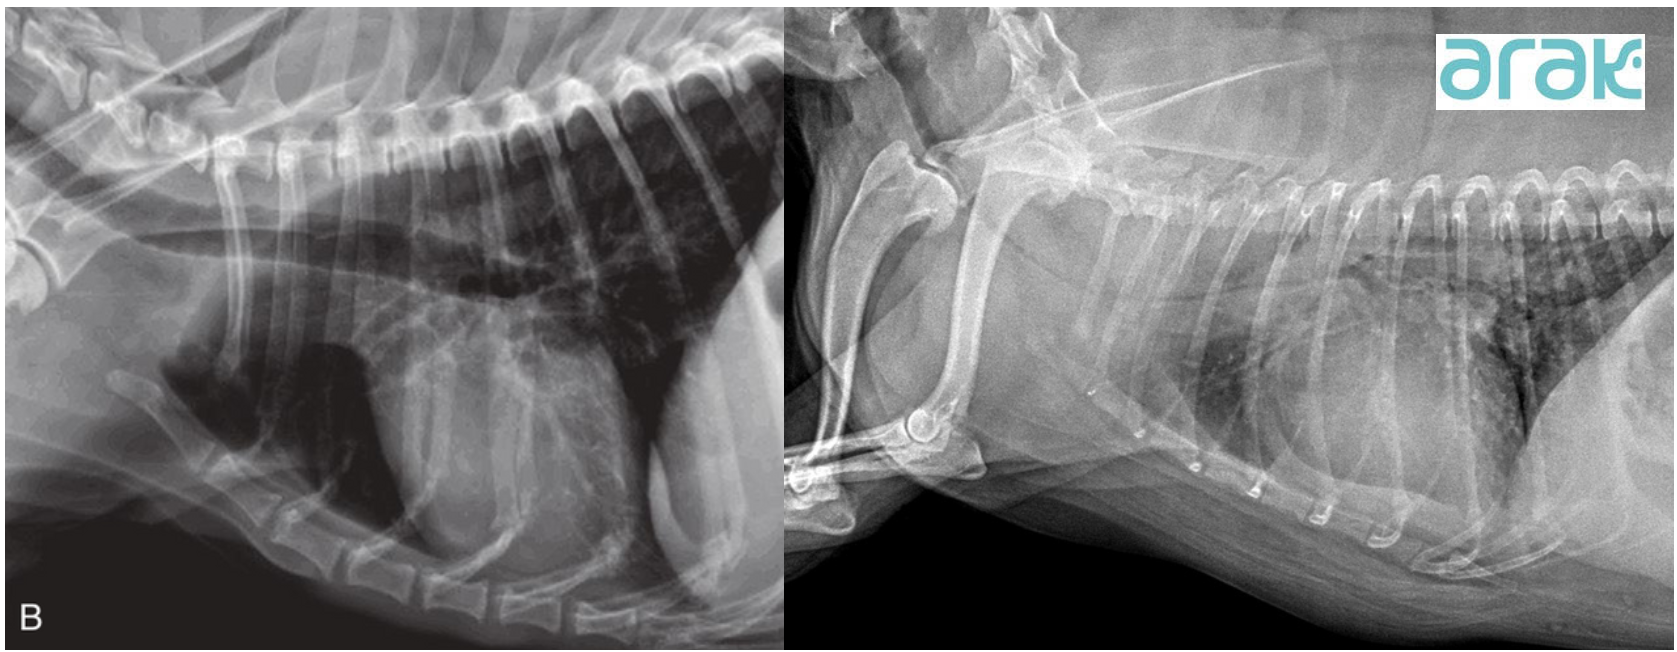

การวินิจฉัยภาวะหลอดลมตีบในสุนัข

สุนัขที่เข้ามาในโรงพยาบาลสัตว์อารักษ์ด้วยอาการเหล่านี้ สัตวแพทย์จะทำการตรวจวินิจฉัยได้จากการตรวจร่างกายทั่วไป การฟังเสียงทางเดินหายใจ เอกซเรย์ช่องอก เอกซเรย์ภาพเคลื่อนไหว (Fluoroscopy) ที่สามารถดูการเปลี่ยนแปลงของท่อลมขณะหายใจเข้า-ออกได้ทันที (Real time) และ การส่องกล้องตรวจทางเดินหายใจ (Endoscopy)